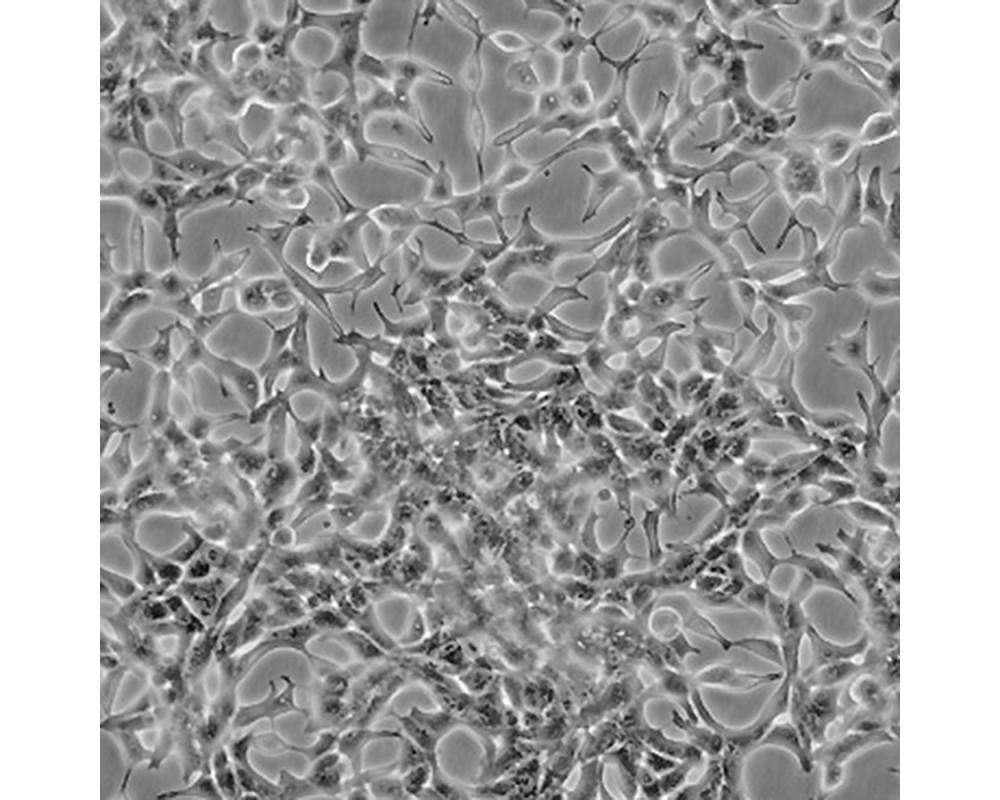

LNCaP clone FGC [LNCaP.FGC]

人前列腺癌細(xì)胞

前列腺癌;左鎖骨上淋巴結(jié)轉(zhuǎn)移;男性

形態(tài)特征

上皮細(xì)胞

生長特性

人前列腺癌細(xì)胞LNCaP克隆FGC是從一位50歲白人男性(血型B+)的左鎖骨淋巴結(jié)針刺活檢中分離,該患者經(jīng)確診為前列腺癌轉(zhuǎn)移。 這株細(xì)胞對5-α-二氫睪酮(生長調(diào)節(jié)子和酸性磷酸脂酶產(chǎn)物)有響應(yīng)。 這株細(xì)胞并不形成一致的單層,而是形成集落,在傳代時可以用滴管反復(fù)吹吸打碎。 它們僅僅輕輕地吸附在基底上,不形成匯合,很快使培養(yǎng)基變酸。 生長很慢。 傳代后48小時內(nèi)不應(yīng)擾動。 當(dāng)培養(yǎng)瓶封包后,多數(shù)細(xì)胞從培養(yǎng)瓶底分離,懸浮在培養(yǎng)基中。 收到后,在通常培養(yǎng)單層細(xì)胞的條件下培養(yǎng)24到48小時,以合細(xì)胞再貼壁。